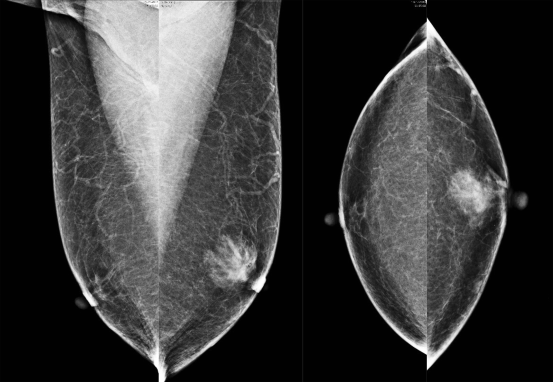

Figuur 1

Standaardmammogram, MLO-opnamen en CC-opnamen van dense mammae.

Tijdens een standaardmammogram worden van elke mamma minstens twee foto’s gemaakt (fig. 1). Dit onderzoek kan worden aangevuld met een vergrotingsopname of een opname van een detail, maar steeds vaker is de mammograaf uitgerust met tomosynthese. Hiermee wordt een serie opeenvolgende röntgenopnamen gegenereerd, waardoor het borstklierweefsel driedimensionaal kan worden afgebeeld, als het ware in dunne plakjes. In een Noorse screeningsstudie leidde tomosynthese tot een verbetering van de tumordetectie [5].

Een mammogram geeft een goed overzicht van het borstklierweefsel en kan tumoren onderscheiden en calcificaties detecteren die op ductaal carcinoma in situ kunnen wijzen. Ook de reproduceerbaarheid, waardoor het mogelijk is te vergelijken en veranderingen te ontdekken, maakt dat het mammogram nog steeds het onderzoek van eerste keuze is bij mammapathologie.